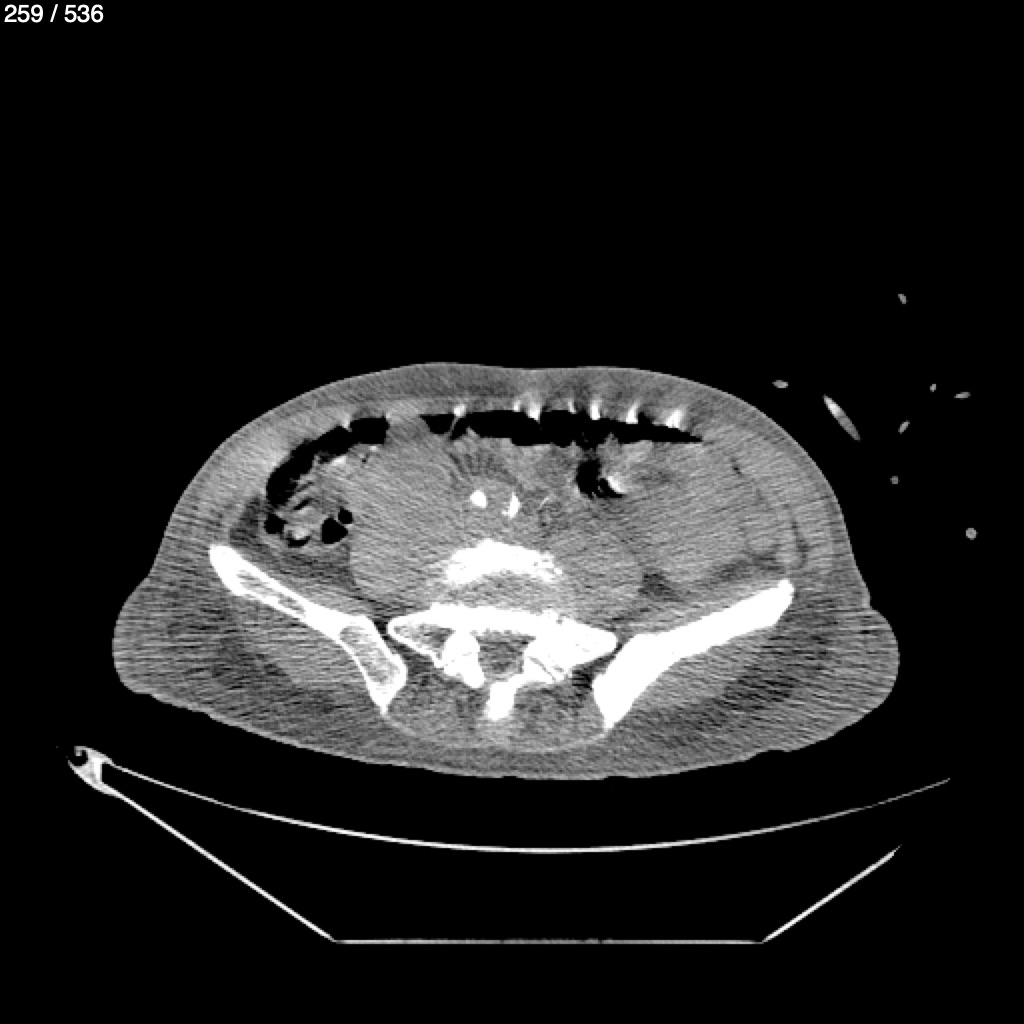

Angel Villalobos Palomeque 73 A - T.C Abdomen Simple